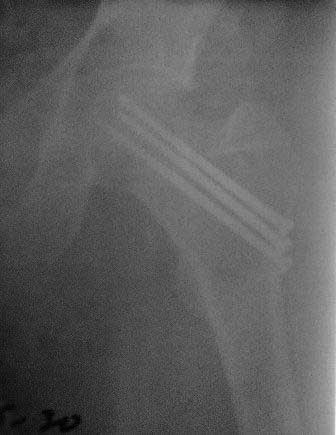

Уважаемые коллеги! Обратился б-ной около 40 лет, три месяца назад оперирован в г.Алмате. При осмотре - ходит c двумя костылями, беспокоят постоянные боли, симптом прилипшей пятки положительный, посмотрел под Р-скопией; сращения нет. Понимаю, показано эндопротезирование, но можно ли органосохраняющие операции с аутопластикой? Если можно, примеры из практики! С уважением Абдурашид. P.S. Р-снимки сразу после операции, и вчерашные.

В данном случае не стал бы разбирать ошибки остесинтеза. На снимке, возможно, из-за большого диаметра шейки шурупы кажутся менее тонкими, чем в 6.5мм. Если установлены стандартные шурупы, тогда, возможно, это случай,

где вместе трех шурупов можно было бы установить 4 в виде ромба?